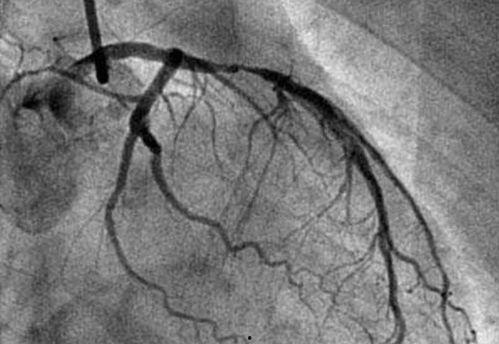

1. 心脏检查:通过心脏造影,医生可以清晰地看到心脏的血管情况,判断是否存在狭窄、堵塞等问题。